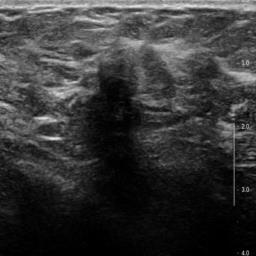

Ultrasonography is an important routine examination for breast cancer diagnosis, due to its non-invasive, radiation-free and low-cost properties. However, it is still not the first-line screening test for breast cancer due to its inherent limitations. It would be a tremendous success if we can precisely diagnose breast cancer by breast ultrasound images (BUS). Many learning-based computer-aided diagnostic methods have been proposed to achieve breast cancer diagnosis/lesion classification. However, most of them require a pre-define ROI and then classify the lesion inside the ROI. Conventional classification backbones, such as VGG16 and ResNet50, can achieve promising classification results with no ROI requirement. But these models lack interpretability, thus restricting their use in clinical practice. In this study, we propose a novel ROI-free model for breast cancer diagnosis in ultrasound images with interpretable feature representations. We leverage the anatomical prior knowledge that malignant and benign tumors have different spatial relationships between different tissue layers, and propose a HoVer-Transformer to formulate this prior knowledge. The proposed HoVer-Trans block extracts the inter- and intra-layer spatial information horizontally and vertically. We conduct and release an open dataset GDPH&GYFYY for breast cancer diagnosis in BUS. The proposed model is evaluated in three datasets by comparing with four CNN-based models and two vision transformer models via a five-fold cross validation. It achieves state-of-the-art classification performance with the best model interpretability.

翻译:超声波分析是乳腺癌诊断的一个重要常规检查,原因是其非侵入性、无辐射和低成本的特性。然而,由于其内在局限性,它仍不是乳腺癌的第一线筛选测试。如果我们能够精确地通过乳房超声图像诊断乳腺癌(BUS),它将是一个巨大的成功。我们提出了许多基于学习的计算机辅助诊断方法,以实现乳腺癌诊断/感官分类。然而,其中多数方法需要事先确定性能模型,然后对ROI内部的跨值进行分类。常规分类支柱,如VGG16和ResNet50等,可以在没有ROI要求的情况下实现有希望的分类结果。但是这些模型缺乏可解释性,从而限制了其在临床实践中的使用。在本研究中,我们提出了一个新的无乳腺癌诊断模型,在超声波图像中进行解释性特征描述。我们利用了先前的解剖学学学知识,即恶性肿瘤和良性肿瘤模型在不同组织层之间有着不同的空间关系,并提议采用状态解析法来编制这一先前的知识。拟议中的HOVer-Trans-Trading-Tradef-trainal Ex-deal-dealal-deal-deal-deal-degraphal-deal-deal-deal-deal-deal-deal disal disal-dal-dal-dal-dal-dal-deal-deal-dal-deal-deal-deal-dal-dal-dal-dal-dal-dal-dal-dal-dal-dal-dal-dal-dal-dal-I-dal-Iversal-dal-Ial-d-d-I-d-d-I-I-I-I-I-I-I-I-I-I-I-I-I-I-I-I-I-I-I-I-I-I-I-I-I-Ial-I-Ial-Ial-I-I-I-I-I-I-I-I-I-I-I-I-I-I-I-I-I-I-I-I-I-I-I-I-I-I-I-I-I-I-I-I-